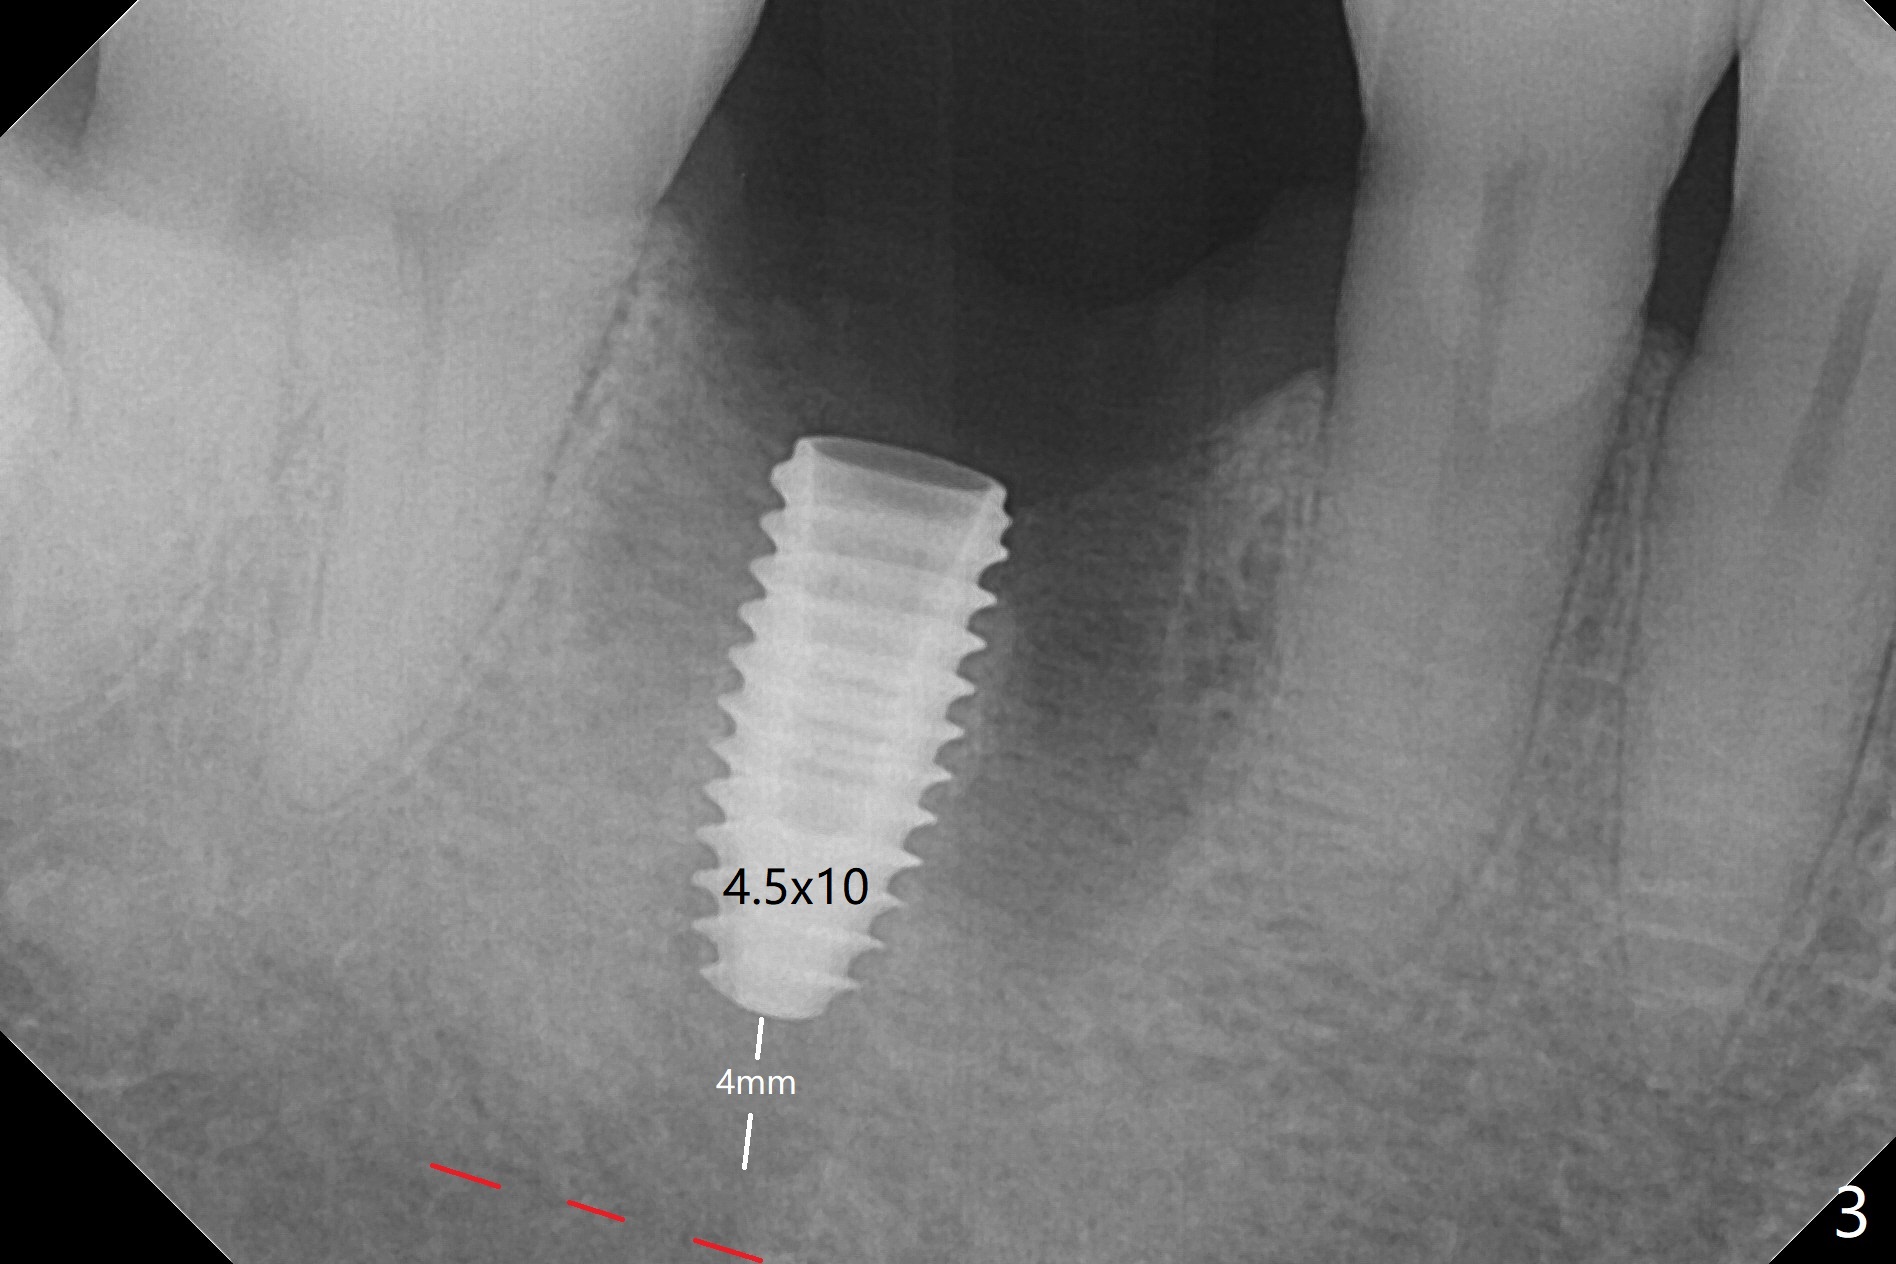

After extraction of the tooth #30, the mesiobuccal plate is found to be lost, corresponding to the fistula (Fig.1 <). Osteotomy is initiated in the flattened septum (lingual) for 13 mm (Fig.2). The patient feels pain when larger drills are being used. Marcaine has to be injected in an infiltration manner for pain control. When a 4.5x10 mm dummy implant is inserted with 55 Ncm, the end of the osteotomy (Fig.3 white line) is close to the Inferior Alveolar Canal (red dashed line). When a definitive implant (Fig.4: 4.5x11.5 mm) is placed with primary stability, there is an apical space (Fig.5 white double arrows). There is moderate postop pain. A shorter implant (10 mm) should be tried when the bone is dense. It will be associated with less pain. The fistula disappears 7 days postop (Fig.6). Although the patient appreciates that the pain is gone, there is atrophy mesiobuccally 2 months postop (Fig.7 *). The implant seems to be have been placed too buccally (Fig.8). With loss of the buccal plate, the implant should be placed away from it to prevent periimplantitis. The abutment is changed from 6.5x4(4) to 6.5x5.5 (3) mm with fabrication of a new provisional. The buccal margin is still supragingival 6 months postop and prep lower before impression. The mesial and distal sockets appear to have healed (Fig.9). When the crown is cemented, the mesiobuccal papilla is present (Fig.10 *), while the mesiolingual one is apparently absent (Fig.11 *). Using a temporary abutment and relining the provisional multiple times would increase the chance of rebuilding the missing papilla. The bone density around the implant increases 11 months post cementation (Fig.12). The dense (apparently cortical) bone seem to grow over the implant plateau 11 months post cementation (Fig.13 <).